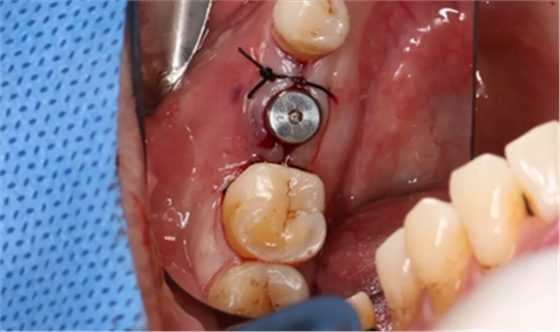

组织瓣复位,常规间断缝合。

(摄于2017年4月14日)